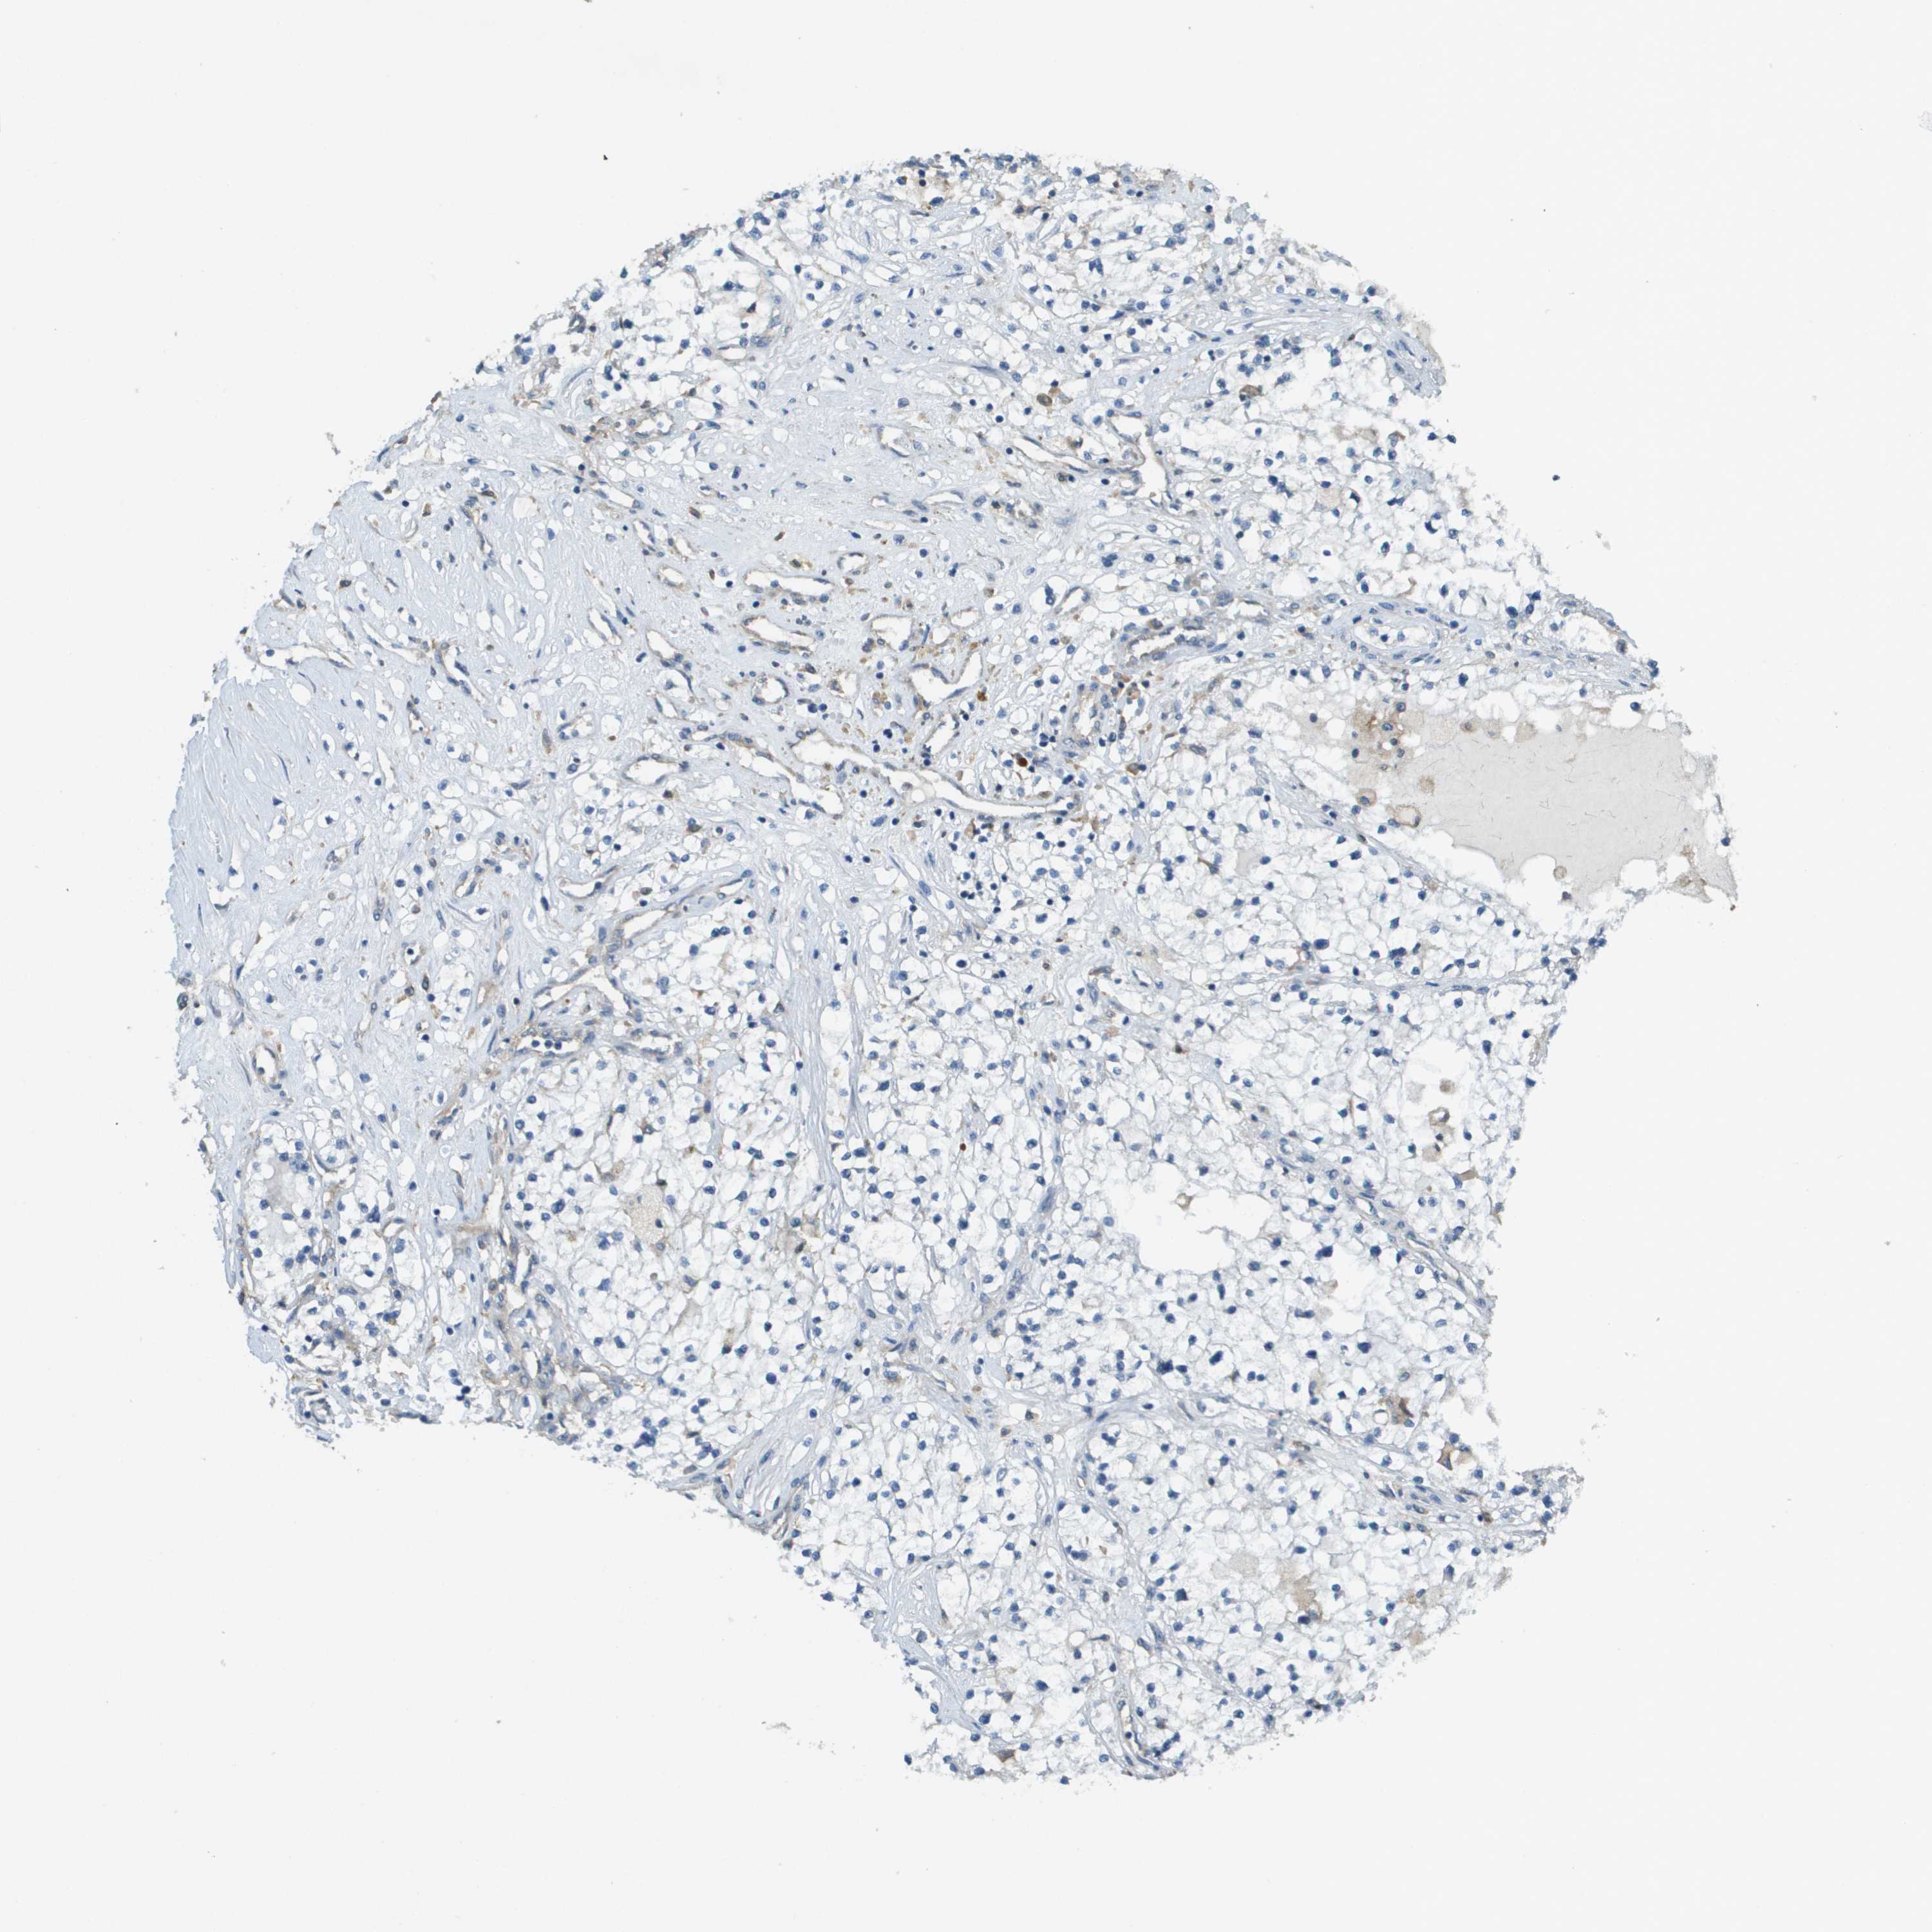

KIDNEY RENAL CLEAR CELL CARCINOMA (VALIDATION) - Interactive survival scatter ploti

The Survival Scatter plot shows the clinical status (i.e. dead or alive) for all individuals in the patient cohort, based on the same data that underlies the corresponding Kaplan-Meier plots. Patients that are alive at last time for follow-up are shown in blue and patients who have died during the study are shown in red.

The x-axis shows the expression levels (FPKM) of the investigated gene in the tumor tissue at the time of diagnosis. The y-axis shows the follow-up time after diagnosis (years). Both axes are complimented with kernel density curves demonstrating the data density over the axes. The top density plot shows the expression levels (FPKM) distribution among dead (red) and alive patients (blue). The right density plot shows the data density of the survived years of dead patients with high and low expression levels respectively, stratified using the cutoff indicated by the vertical dashed line through the Survival Scatter plot. This cutoff is automatically defined based on the FPKM cutoff that minimizes the p-score. The cutoff can be changed by dragging the vertical line or by entering a cutoff value in the square labeled "Current cut-off".

Under the Survival Scatter plot the p-score landscape (black curve; left axis) is shown together with dead median separation (red curve; right axis). Dead median separation is the difference in median mRNA expression between patients who have died with high and low expression, respectively. It is calculated as follows: median FPKM expression of dead patients with high expression - median FPKM expression of dead patients with low expression. This is intended to aid the user in visually exploring custom cutoffs and the associated p-scores and dead median separation.

Individual patient data is displayed and can be filtered by clicking on one or more of the category buttons on the top of the page. Categories describing expression level and patient information include: high, low, alive, dead, female, male and tumor stages. The scale of the x-axis can be toggled between linear and log-scale by clicking on the "x log" button. Mouse-over function shows TCGA ID, patient information and mRNA expression (FPKM) for each patient.

& Survival analysisi

Kaplan-Meier plots summarize results from analysis of correlation between mRNA expression level and patient survival. Patients were divided based on level of expression into one of the two groups "low" (under cut off) or "high" (over cut off). X-axis shows time for survival (years) and y-axis shows the probability of survival, where 1.0 corresponds to 100 percent.

CORO1B is not prognostic in Kidney Renal Clear Cell Carcinoma (validation)

Best expression cut offi

Based on the FPKM value of each gene, patients were classified into two groups and association between prognosis (survival) and gene expression (FPKM) was examined. The best expression cut-off refers the FPKM value that yields maximal difference with regard to survival between the two groups at the lowest log-rank P-value. Best expression cut-off was selected based on survival analysis .

When clicking on this number, the vertical dashed line indicating cut-off, the interactive survival plot, and the Kaplan-Meier curve will be adjusted to show results based on the best expression cut-off.

: 65.82

P scorei

Log-rank P value for Kaplan-Meier plot showing results from analysis of correlation between mRNA expression level and patient survival.

N/A

TCGA RNA samplesi

RNA-seq data is reported as average FPKM (number Fragments Per Kilobase of exon per Million reads), generated by the The Cancer Genome Atlas (TCGA) .

Normal distribution across the dataset is visualized with box plots, shown as median and 25th and 75th percentiles. Points are displayed as outliers if they are above or below 1.5 times the interquartile range. FPKM values of the individual samples are presented next to the box plot.

Average pTPM 57.8

Number of samples 100